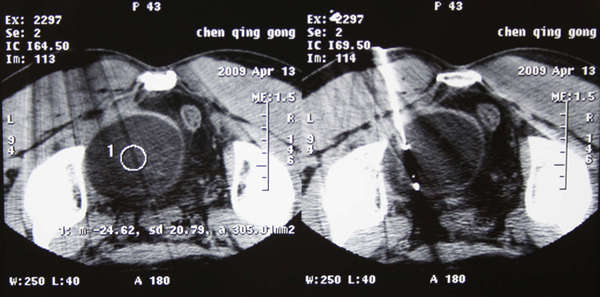

经皮冷冻最常用系应用超声或CT引导下,将冷冻探针插入肿瘤内,输入高压氩气使探针尖端的靶组织冷却至-160℃,导致靶组织结冰、细胞膜破裂及细胞内容物释放引起微血管闭塞、组织缺血坏死。

然后改输入氦气,使冰球复温,然后再作冷冻―>复温,至少2个循环(cycles)。冷冻持续至冰球覆盖整个肿瘤及其周围5-10毫米的正常组织。对于大的肿瘤,常需同时插入多根冷冻探针冷冻。根据需要,有时要作至少2-3次冷冻治疗,可提高消融效果,杀灭肿瘤细胞,达到治疗肿瘤的目的。

手术常用冷冻探针直径有1.47mm、1.7mm、2.0mm及3.0mm。使用不同规格的冷冻探针,术中所形成的“冰球”大小不一。探针直径越小形成的“冰球”越小,组织损伤越轻,反之亦然。